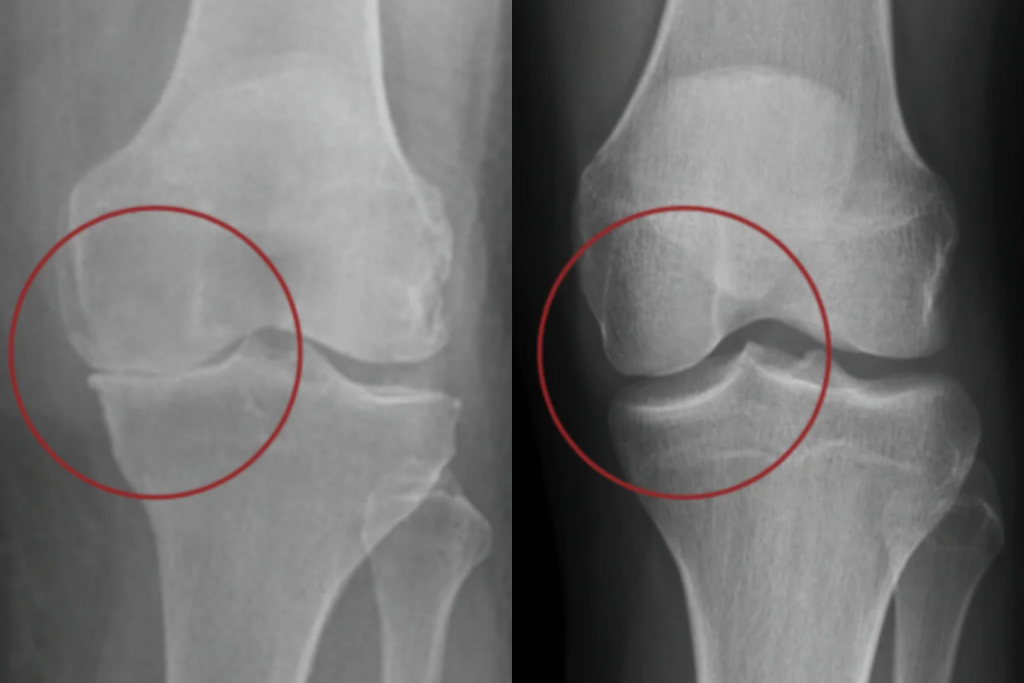

Bahnbrechende Forschung enthüllt die versteckte Arthrose-Krise

Wissenschaftler haben entdeckt, dass der Rückgang der Gelenkflüssigkeit der zentrale Auslöser für Arthrose ist. Denn die Gelenkflüssigkeit versorgt den Knorpel mit Nährstoffen – fehlt sie, baut sich der Knorpel langsam ab, bis die Knochen schmerzhaft aneinander reiben.

Das Gelenk verliert dadurch seine Schutzfunktion – was zu Folgendem führt:

⚠️ Humpeln, steifem Gang und Problemen beim Aufstehen

⚠️ Bewegungsverweigerung bei Treppen, langen Wegen oder Spielen

⚠️ Reibung zwischen den Knochen, die Schmerzen bei jeder Bewegung verursach

⚠️ Entzündungen, die den Abbauprozess weiter verschärfen